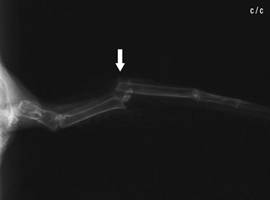

Patient after the

operation: Internal fixation of a broken radius with an

intramedullary pin (IM pin, arrow: nail exit). Photo: C. Haupt

Radius fracture,

dislocated |

Radius fracture

after intramedullary pinning with a 0.4 mm

cannula |

The relatively frequent

radius fracture, which, if not treated, can lead to limited flight

ability, is pinned by using a 0.4 mm cannula, which is inserted into

the distal end of the fracture, exits through the radius head which

is palpable at the shoulder joint and is retrogradely pushed into

the proximal end of the fracture as far as just in front of the

elbow joint. The pin coming out at the shoulder joint is released 1

- 2 mm over the skin, and is protected with a small adhesive strip,

so that the patient is unable to pull it out.